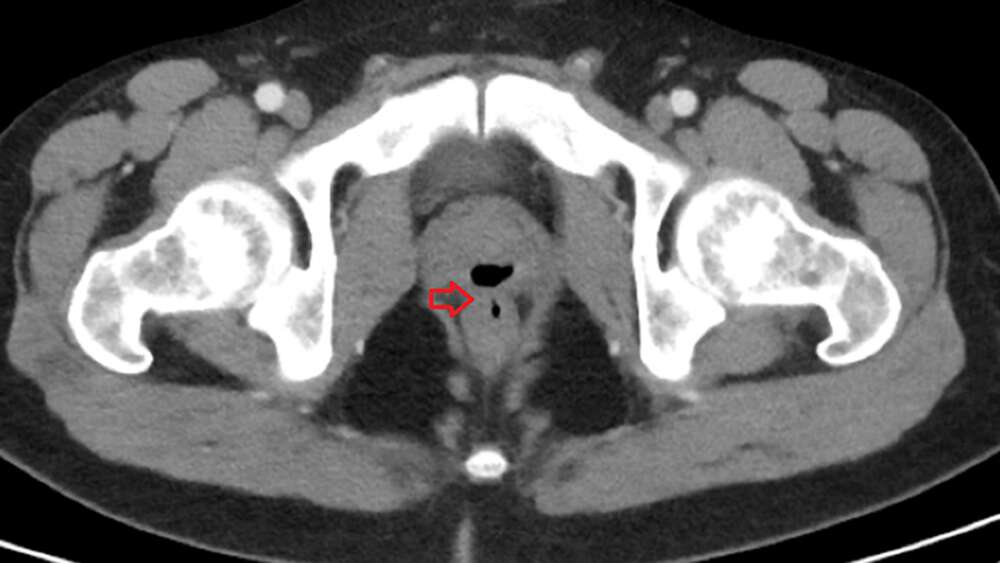

Компютърната томография най-накрая разкрива същината на проблема.

Източник: Cureus (CC by 4.0)

Лекарите откриват „пълна с газ структура“. Допълни тестове потвърждават присъствието на фистула (анормален канал) между пикочния канал и ануса. Именно оттук минават различните течности и твърди елементи. Докато поправя фистулата по хирургичен екип, екипът решава да потърси и потенциалните причини за появата на този проблем, но отхвърля варианти като туберкулоза, възпалително заболяване на червата, ректална травма или пенетрация.